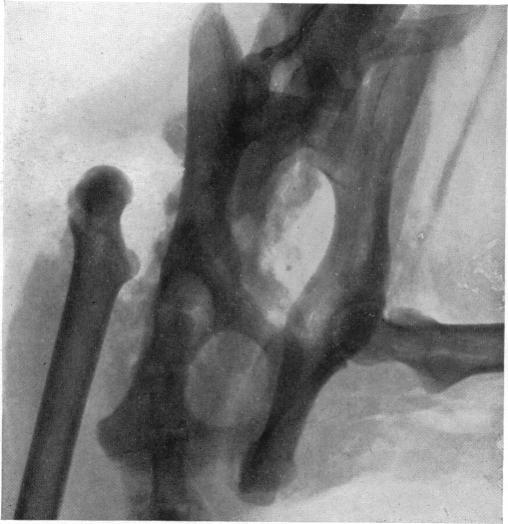

ON THE NATURE OF NEUROPATHIC AFFECTIONS OF THE JOINTS.

Ann Surg. 1917 Aug;66(2):201-7. doi: 10.1097/00000658-191708000-00011.